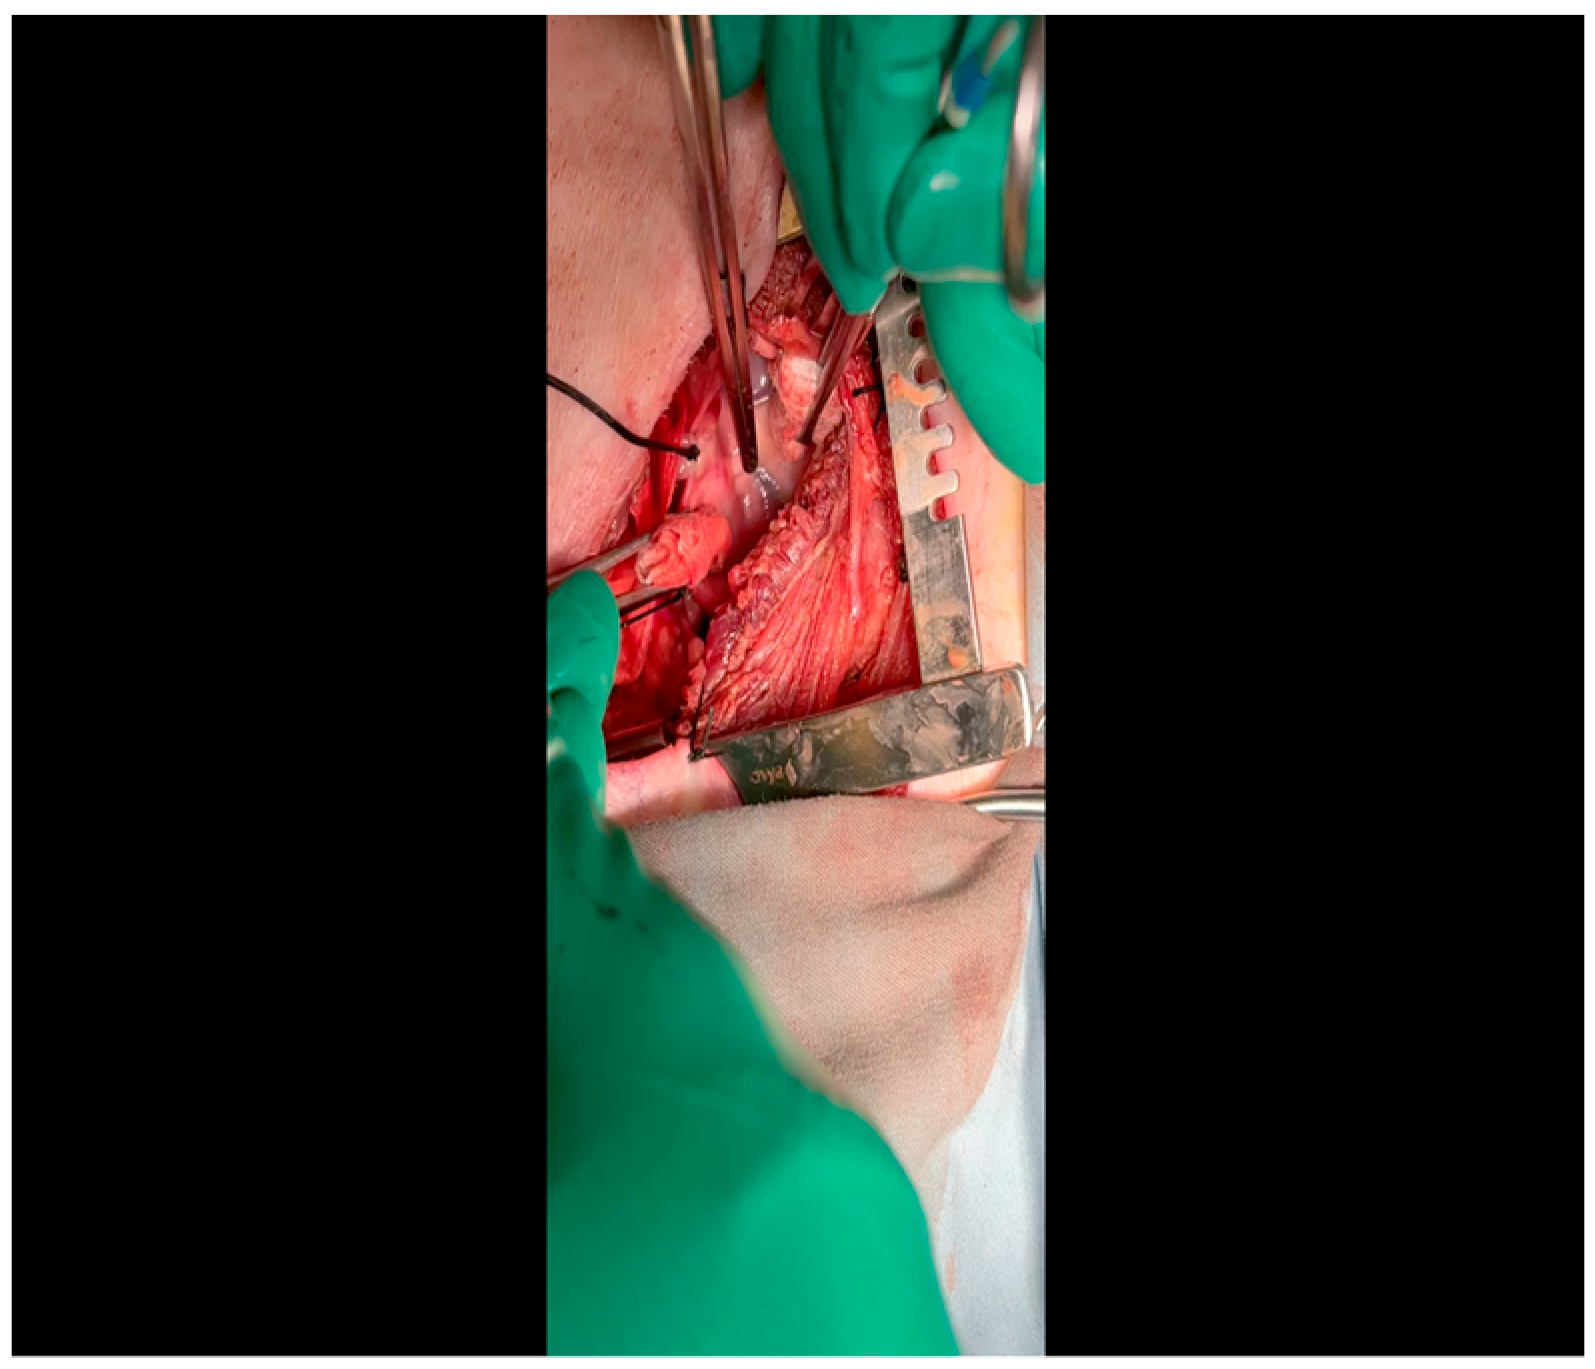

- The pericardium is opened (Figure 3) with scissors. It is important to identify and protect the phrenic nerve.